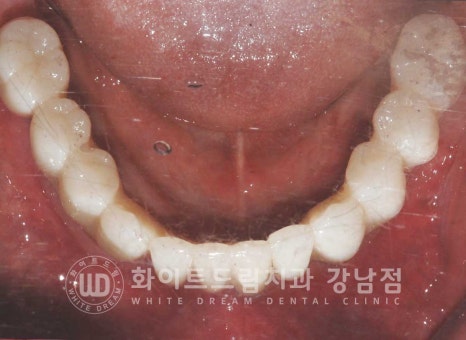

환자분의 치료 전/후 사진입니다.

[동일 인물이며 동일 환경에서 촬영되었습니다.]

기간 : 24.04.29 - 24.10.10

이렇게 잃어버린 전체 치아를 다시 완성하는데

수술 후 총 5회의 내원만 해주셨고

전체 임플란트 치료 기간도 6개월이 채 되지 않게 완료가 되었습니다.